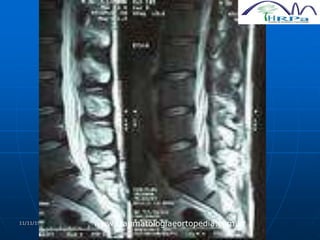

HÉRNIA LOMBAR

 Mais freqüente hérnia de disco

 Modic (1986) demonstra que a RNM apresenta a

melhor avaliação dignóstica do que a mielografia

e a TC

 Boden (1990) encontrou 22% de alterações

discais (abaixo de 40 anos), 58% de alterações

discais (acima de 40 anos) na RNM em pessoas

assintomáticas